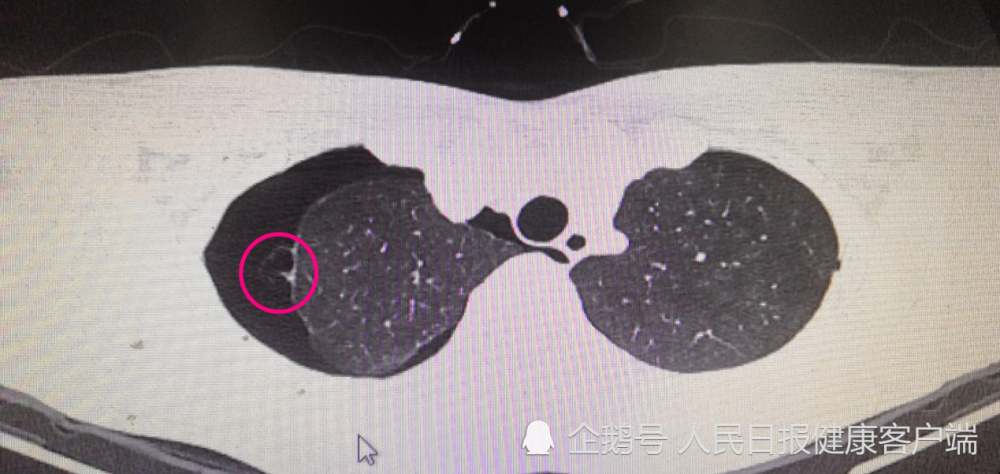

赵忠祥因肺鳞状细胞癌去世肺癌凶猛我们能做些什么

双肺容量增大,血管影减少.在肺裂处可见胸膜增厚或瘢痕.